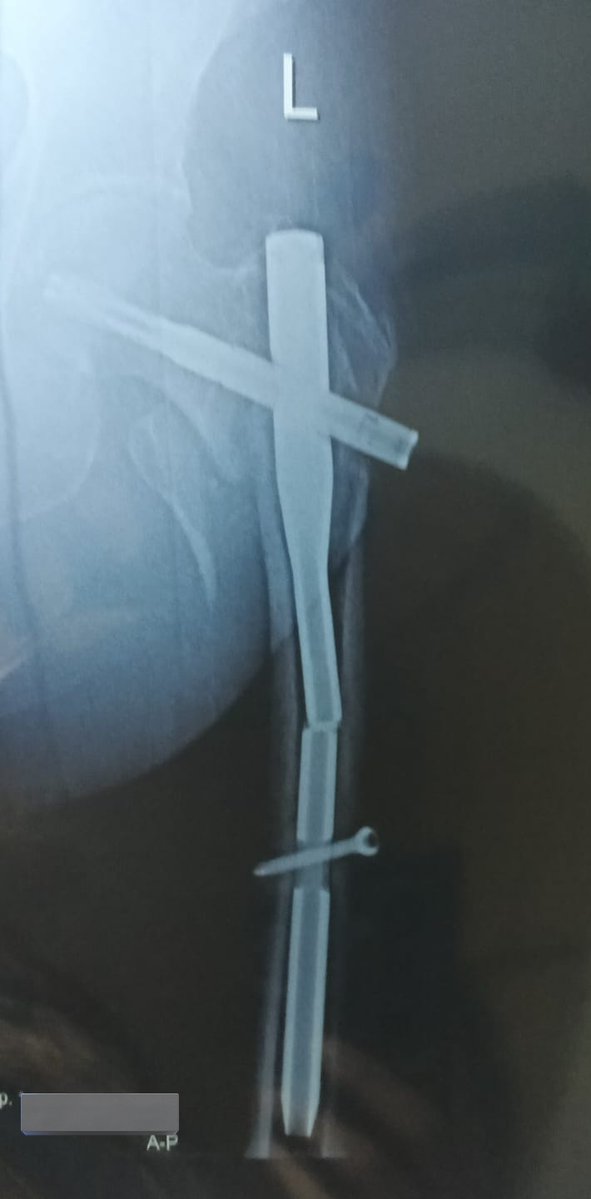

I’m bionic for real now 🦾